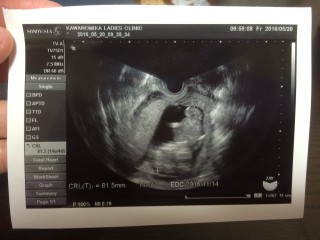

写真:14w0d:まうすさん

体外受精33回目にしての今のところ順調な妊娠生活。今日は、背骨の一本一本、肋骨も見えました!人間の生命力はすごいです!BPD24ミリです。

BPD2.73cm